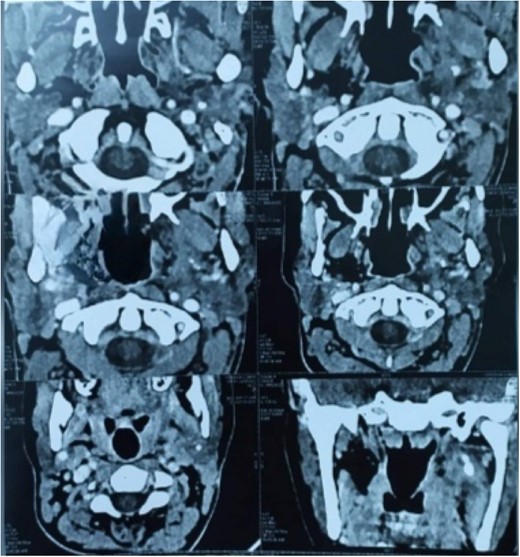

No post-operative complication was noted. Patient was discharged on the second day and came back on the fourth day for drain removal. New CT-scan revealed a successful surgery intervention (Fig. 3). Post-operative antibiotic injection of cefotaxime and injection of metronidazole was given for 5 days, and analgesic treatment with paracetamol 1 g every 6 h in the presence of pain was recommended. Histopathological examination revealed a benign schwannoma. Suture removal of the both incisions performed on the 10th post-operative day (Fig. 4), with a strict oral hygiene recommended to the patient. Up to the last consultation, July 2022, no side effects or complications have been reported.